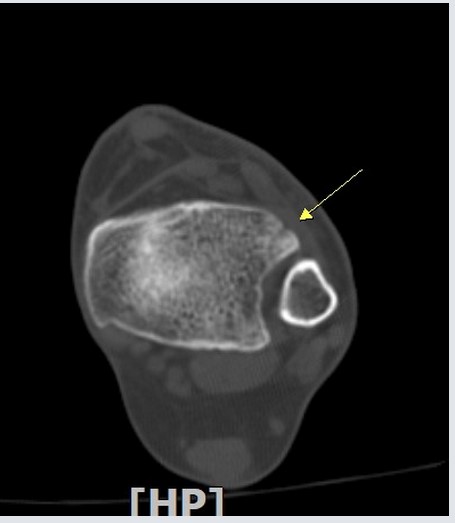

ÃÊÀ½ÆÄ ¼Ò°ß :  ¹ß¸ñ ¾Õ Á¾´Ü¸é°Ë»ç¿¡¼­ ¹ß¸ñ°üÀý³»  ¾à°£ÀÇ ¼ö¾×Àú·ù°¡ °üÂûµÊ(»çÁø 1).